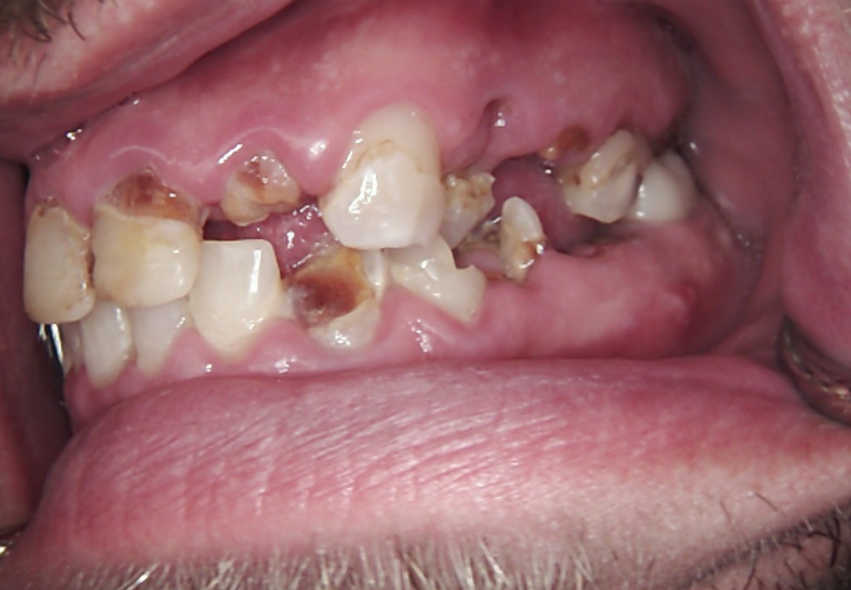

The patient is a relatively young man in recovery from drug addiction. At the time of his initial consultation, he had been living a healthy lifestyle for three years. Restoring his smile was a high priority, as it is crucial not only for esthetics but also for self-confidence, clear speech, and the ability to maintain a nutritious diet without limitations.

Long-term psychoactive substance use had caused severe xerostomia, contributing to the rapid development of dental caries and decay. The teeth in the upper jaw were non-restorable, and many were already missing. The condition of the lower jaw was slightly better: the anterior teeth were in satisfactory condition, but the posterior teeth were severely decayed and required extraction.

The presented images show the patient’s initial dental condition.